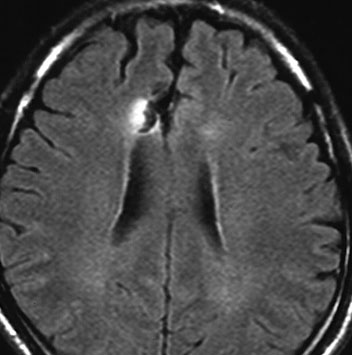

フレア画像です。左上前頭回の星細胞腫ですが,境界がとてもはっきりしていて限局性 localized single gyrus glioma です。びまん性 diffuseには見えません。IDH1の変異があり,1p/19qの欠失はないので星細胞腫グレード2です。上の例とは全く違う臨床像を示しますが,分子病理でも区別はつきません。頑張って早めに全摘出して治してしまった方がいいタイプです。再発を避けるために,supratotal resectionと言って,周囲の正常脳組織も10mmくらい余分に摘出します。